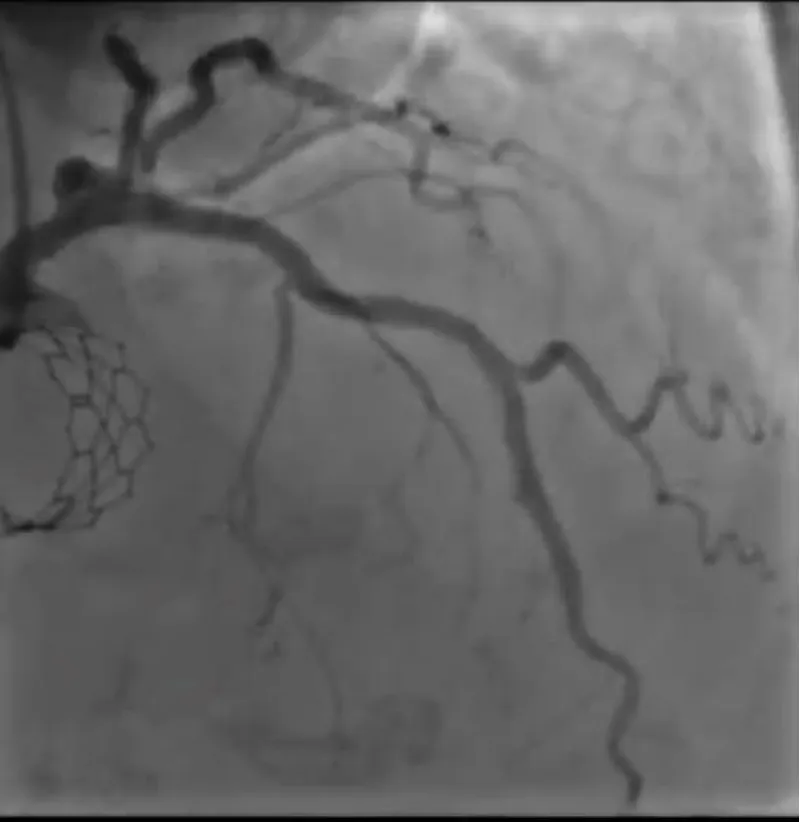

The clinical case concerns an 81-year-old woman with a history of systemic arterial hypertension, hypercholesterolemia, paroxysmal atrial fibrillation, chronic kidney disease, iron-deficiency anemia, and bilateral carotid atheromatosis for which she underwent a Carotid Endarterectomy (CEA) procedure. Additionally, she had a history of breast carcinoma, treated with surgery, subsequent chemotherapy, and ongoing Letrozole therapy. In 2019, the patient presented to the emergency department due to exertional dyspnea and low-threshold angina. During hospitalization, high average ventricular response (109 BPM) atrial fibrillation was diagnosed. Routine lab tests showed rising of hsTN-I (peak 800 pg/dL) and pro-BNP (peak 2476 pg/mL) and anemia Hb 9.1 g/dL. Echocardiography revealed severe depression of the left ventricular function (ejection fraction of 30%, with antero-apical akinesia) and low-flow-low-gradient aortic stenosis (mean gradient of 26 mmHg and AVAi of 0.5 cmq/m2 and SVi 29 mL/m2). So it was performed a Dobutamine stress Echo showed a rise of SVi up to 38 mL/m2 and a mean aortic gradient of up to 48 mmHg. Coronary angiography showed the right dominant coronary artery, of good caliber and course, with no angiographically significant lesions (Figure 1). The Left Main artery, with good caliber, had a 90% calcific stenosis at the distal segment, involving the proximal segment of the Left Anterior Descending artery. The Left Circumflex artery, with good caliber and course, presented a 30% ostial stenosis. The Intermediate Branch, with good caliber and course, showed 80% stenosis at the proximal segment (Figure 2). The Left Anterior Descending artery, also of good caliber and course, was diffusely atherosclerotic with a long, severely calcific 80% stenosis at the mid-distal segment (Figure 3). Therefore, the case was discussed by a multidisciplinary Heart team at our center. The STS score calculated indicated a mortality risk of 11.4%. Due to this high risk, surgical treatment was not considered, and the patient underwent a four-step percutaneous intervention. Before the intervention, a CT angiography was performed, revealing an aortic annulus area of 433.2 mm2, a perimeter of 75.3 mm, and a coronary height from the annulus of 10 mm. The right common femoral artery mean diameter was 6.1 mm2 and the external iliac artery was 8.4 mm2 with moderate tortuosity without significant calcification (Figure 4-6). Therefore, a 23 mm Edwards Sapien 3 valve was chosen. Our strategy consisted of 4 steps:

Figure 1: Right dominant coronary artery, of good caliber and course, with no angiographically significant lesions.